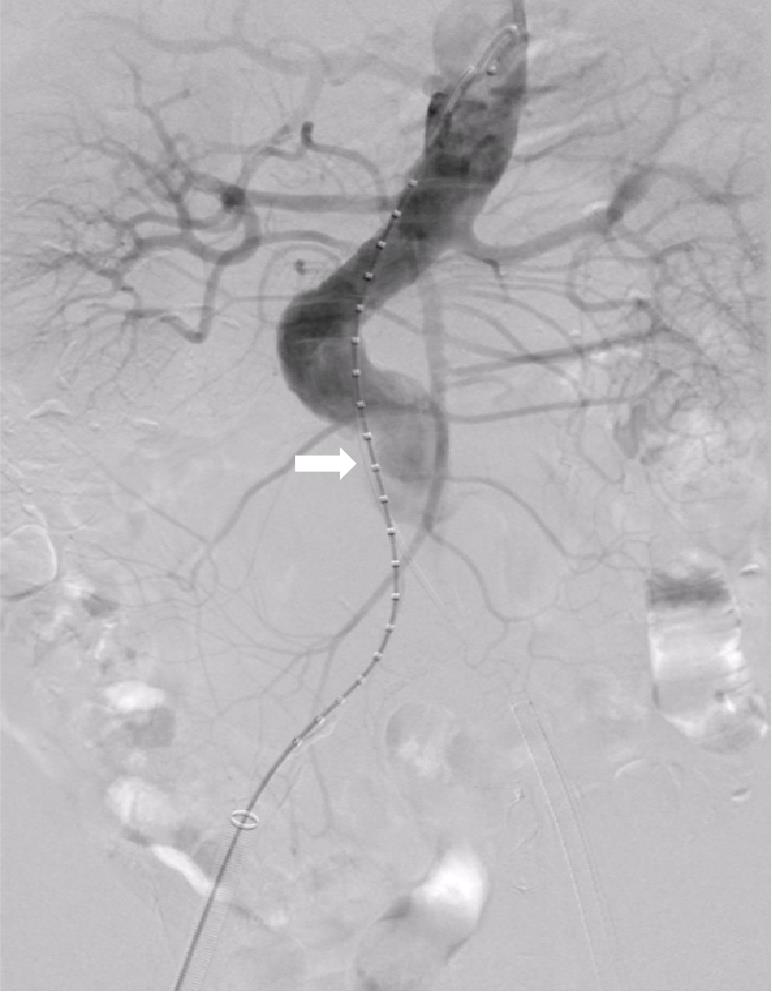

图2 预留5 F导管下移至瘤颈末端的瘤腔顶点Fig.2 The reserved 5 F catheter advanced downward to the apex of the aneurysm sac at the distal end of the aneurysm neck